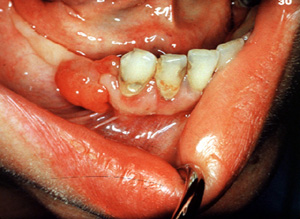

Irritación menor que causa proliferación de tejido de granulación excesiva, puede indicar  una enfermedad sistémica. Ésta es una mujer de 25 años de edad, que padece de diabetes desde los 8 años de edad.